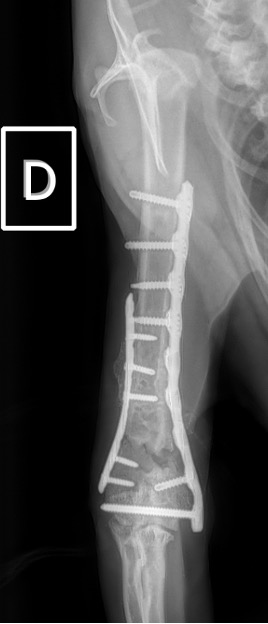

Exemple 3 :

Figure 9 : Pré-Op

Figure 10 : Opération

Figure 11 : Post-Op Immédiat

Figure 12 : Post-Op 1 mois

L’avènement récent des plaques anatomiques constitue une nouvelle option dans le traitement de ces fractures : dans l’exemple 3 (chat Ragdoll), une plaque anatomique médiale de 2 mm acceptant des vis de 1,6 et 2 mm a été utilisée seule avec succès.